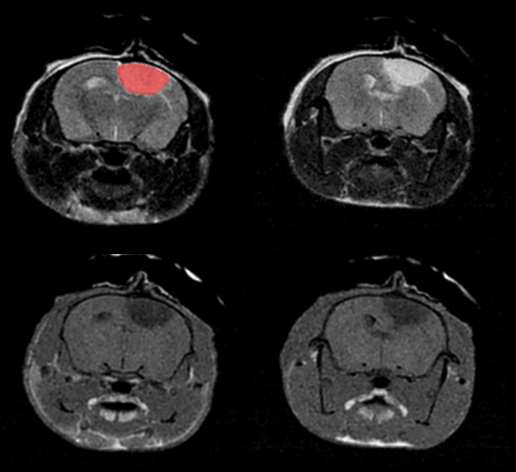

T2- (top row) and T1- (bottom row) weighted images show stroke lesion and its segmentation (in red) within the rat brain. Scintica Instrumentation Inc

Monitoring the growth of xenograft tumor grown in the mouse hindlimb is identified with T2-weighted images. Segmentation of tumor region of interests (in red) on each tumor-containing slice allows accurate volume quantification. Image Credit: Scintica Instrumentation Inc

Hindlimb tumor growth: Monitoring the growth of xenograft tumor grown in the mouse hindlimb is identified with T2-weighted images. Segmentation of tumor region of interests (in red) on each tumor-containing slice allows accurate volume quantification. Image Credit: Scintica Instrumentation Inc